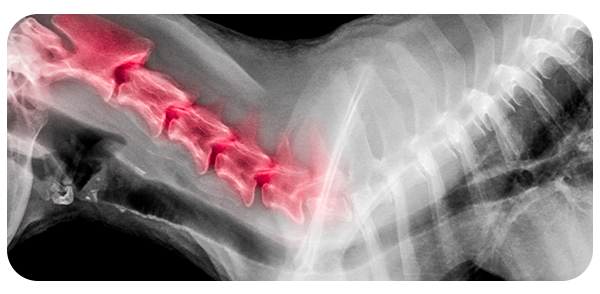

Para quem é indicado o procedimento minimamente invasivo da coluna?

O procedimento minimamente invasivo é indicado, para o tratamento de dor nas costas (lombalgia), dor cervical (pescoço), dor ciática, hérnia de disco lombar ou cervical, doença degenerativo discal lombar e cervical, fratura por osteoporose